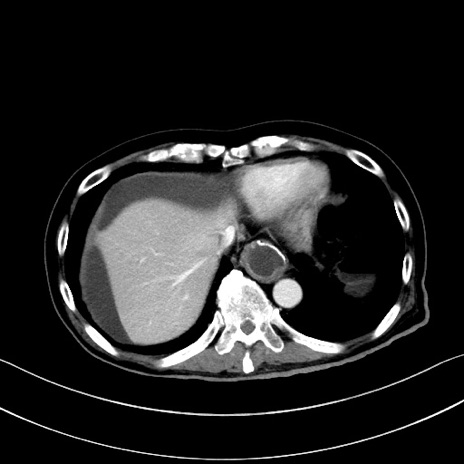

症例28(横断像)

【症例】60歳代男性

【主訴】嘔吐

【現病歴】胃癌にて胃全摘後。食思不振が悪化し、夜中に嘔吐することがある。

【既往歴】胃癌、胃全摘、脾摘、胆摘後

【データ】WBC 5900、CRP 10.56